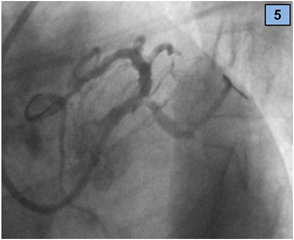

A seven French extra back-up catheter was placed in the ostium of the left coronary artery. Three guidewires were advanced: one in the LAD artery and the other two in the CX artery and branches. While crossing the CX occlusion with the wire, the vessel opened spontaneously (Figure 4) and an image suggestive of thrombotic material was seen in the CX and the second obtuse marginal branch (Figure 5).

Figure 5 The CX artery opened spontaneously after crossing the lesion with the wire.